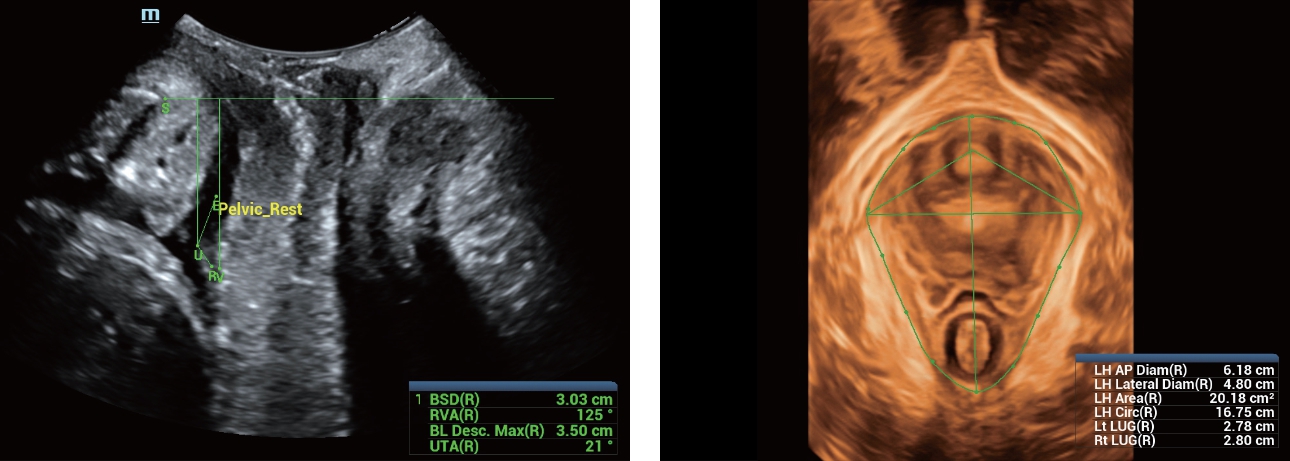

Oprócz uzyskiwania jako?ci obrazu typowego dla aparatów klasy premium, Resona 7 rozszerza mo?liwo?ci klinicznych badań USG dzi?ki rewolucyjnej funkcji V Flow, s?u??cej do oceny hemodynamiki naczyń, a tak?e najlepszej na rynku funkcji inteligentnego, automatycznego uzyskiwania p?aszczyzny na podstawie zestawów danych obj?to?ciowych 3D, umo?liwiaj?cej diagnozowanie stanu Centralnego Uk?adu Nerwowego u p?odu. Aparat Resona 7 ??czy w sobie najbardziej intuicyjn?, wielodotykow? obs?ug? za pomoc? gestów oraz wszystkie kluczowe funkcje kliniczne, co sprawia i? jest prawdziwym liderem we wprowadzaniu innowacji w ultrasonografii.